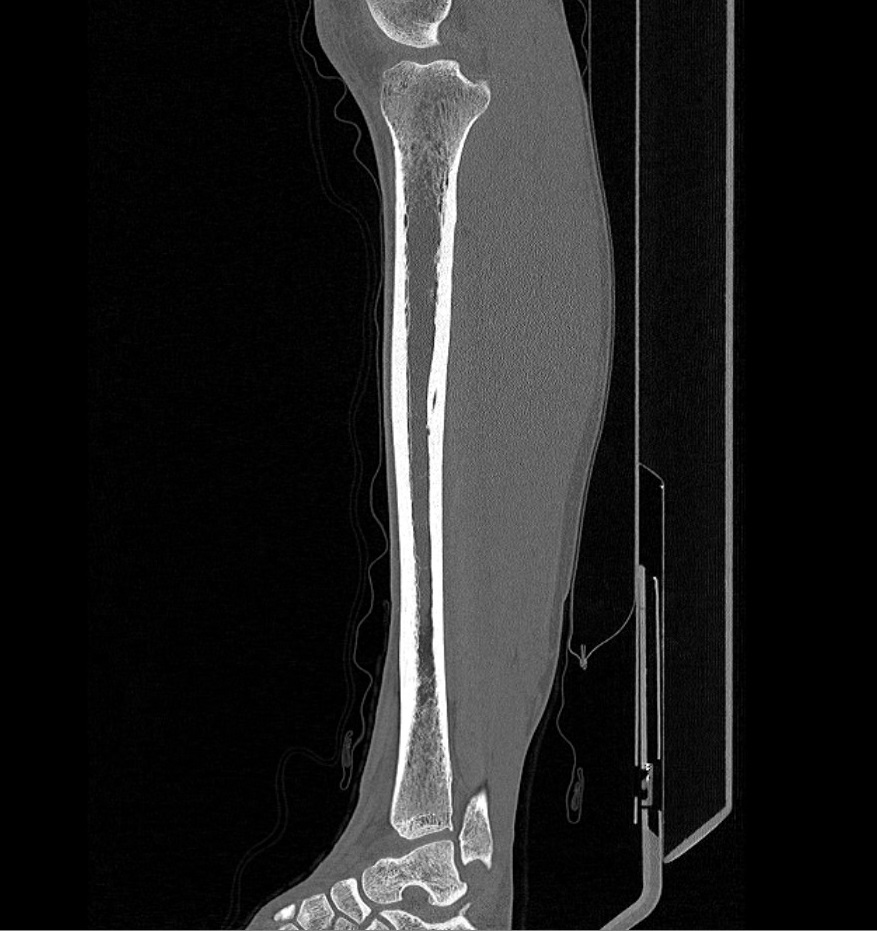

Наиболее информативным методом исследования костных структур и мягких тканей голени является мультиспиральная компьютерная томография. КТ относится к лучевым методам исследования и основана на применении ионизирующего излучения и последующей цифровой обработке данных, полученных при КТ-сканировании.

В наших медицинских центрах обследование области голени проводится на современных мультиспиральных компьютерных томографах последнего поколения TOSHIBA AQUILION. При помощи рентгеновских лучей аппараты послойно сканируют исследуемую область с толщиной среза от 0,5 мм. В результате получаются детальные снимки и цифровые трехмерные изображения в мельчайших подробностях. При этом пациент получает уменьшенную дозу рентгеновского облучения.

Мультиспиральная компьютерная томография позволяет оценить структуру костей голени, выявить переломы, воспалительные изменения, участки деструкции костной ткани, диагностировать опухолевые образования.